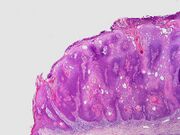

Visual diagnosis is made by the "stuck on" appearance, horny pearls or cysts embedded in the structure. Darkly pigmented lesions can be challenging to distinguish from nodular melanomas.[10] Furthermore, thin seborrheic keratoses on facial skin can be very difficult to differentiate from lentigo maligna even with dermatoscopy. Clinically, epidermal nevi are similar to seborrheic keratoses in appearance. Epidermal nevi are usually present at or near birth. Condylomas and warts can clinically resemble seborrheic keratoses, and dermatoscopy can be helpful to differentiate them. On the penis and genital skin, condylomas and seborrheic keratoses can be difficult to differentiate, even on biopsy.[citation needed]

A study examining over 4,000 biopsied skin lesions identified clinically as seborrheic keratoses showed 3.1% were malignancies. Two-thirds of those were squamous cell carcinoma.[11] To date, the gold standard in the diagnosis of seborrheic keratosis is represented by the histolopathologic analysis of a skin biopsy.[12]

| Common seborrheic keratosis (basal cell papilloma, solid seborrheic keratosis) | Dull or lackluster surface.[2] | |

| Reticulated seborrheic keratosis (adenoid seborrheic keratosis) | Dull or lackluster surface, and with keratin cysts seen histologically.[2] | |

| Stucco keratosis (deratosis alba,[15] digitate seborrheic keratosis, hyperkeratotic seborrheic keratosis, serrated seborrheic keratosis, verrucous seborrheic keratosis) | Common. Dull or lackluster surface, and with church-spire-like projections of epidermal cells around collagen seen histologically.[2][3] Stucco keratoses are often light brown to off-white, and are no larger than a few millimeters in diameter. They are often found on the distal tibia, ankle, and foot.[14] | |

| Clonal seborrheic keratosis | Dull or lackluster surface, and with round, loosely packed nests of cells seen histologically.[2] | |

| Irritated seborrheic keratosis (inflamed seborrheic keratosis, basosquamous cell acanthoma) | Dull or lackluster surface.[2] | |

| Seborrheic keratosis with squamous atypia | Dull or lackluster surface, and with round, loosely packed nests of cells seen histologically.[2] | |

| Melanoacanthoma (pigmented seborrheic keratosis) | Dull or lackluster surface.[2][3] It involves a proliferation of keratinocytes and melanocytes.[16] | |